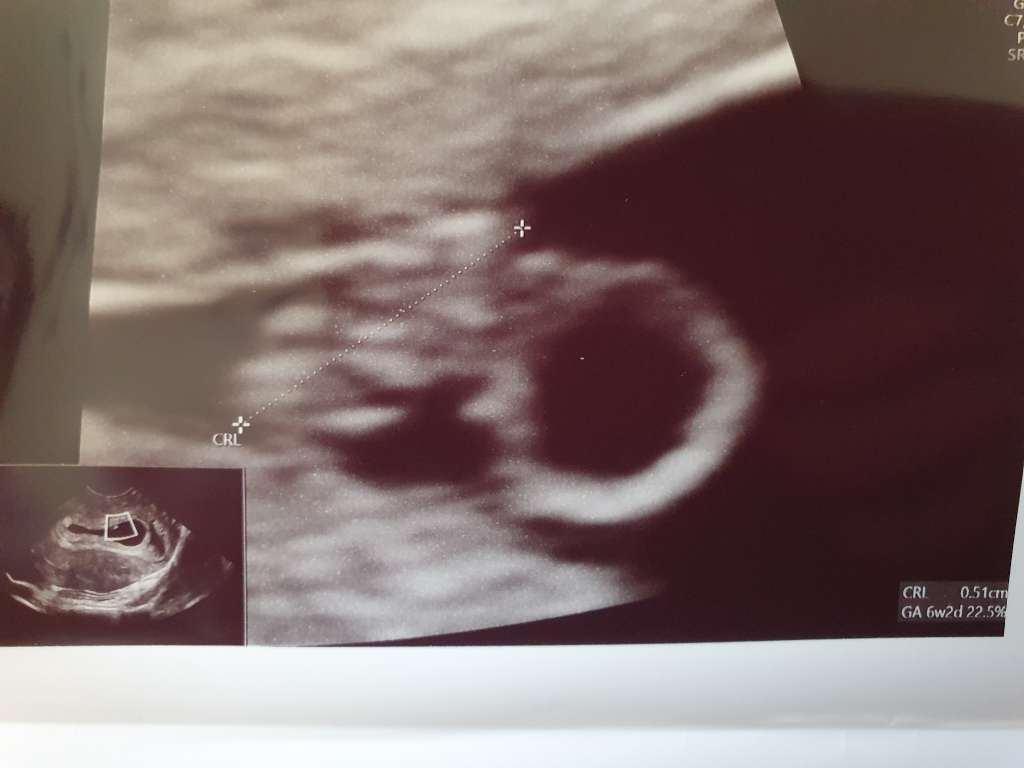

Jestem po wizycie 🙂 kropek jest rowno z terminem OM, czyli 6+2, jest akcja serca 120/min, widzialam jak serduszko pulsuje ale nie sluchalismy 🙂 do zastrzykow dostalam jeszcze wapn, bo skutkiem ubocznym ich jest m.in. osteoporoza no i mam cala liste badan do zrobienia. Bardzo sie ciesze i jeszcze bardziej uswiadomilam sobie ze zaczyna sie kolejna piekna historia naszego zycia 🙂

A tu moj kropek 😍